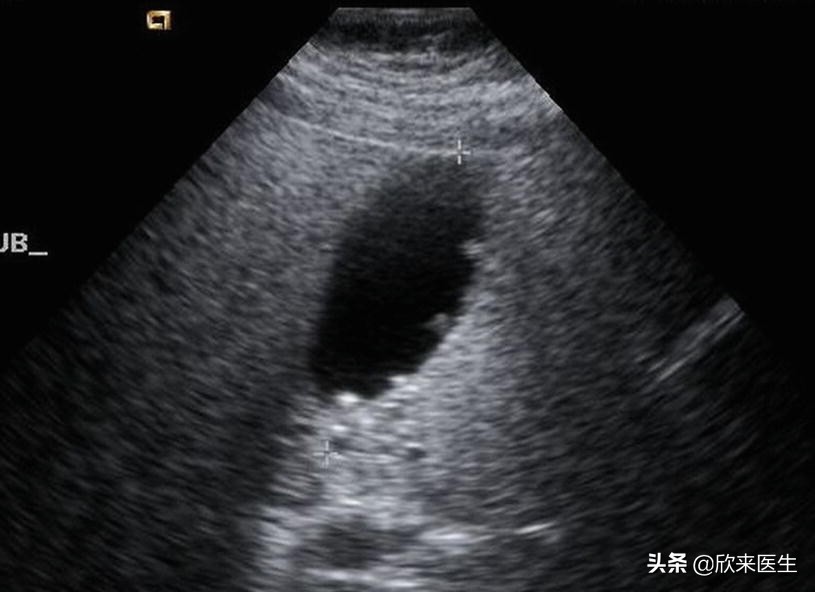

胆囊息肉B超表现

多数人会认为因为年轻人不爱吃早饭导致的,这种说法并没有什么依据。有些医生会认为这与身体代谢脂类的方式有关,当胆固醇过饱和并沉积于胆囊黏膜固有层,进一步侵及黏膜间隙,被巨噬细胞吞噬形成泡沫细胞并在间质层集聚,促进胆囊固醇性息肉的生成,这是目前胆固醇息肉增多的主要原因。但是其发生率与年纪、性别、体重、运动量、喝酒、饮食规律以及血液里的脂类物质都没有必然的联系。目前医学界尚无法完全确认胆囊息肉的病因,但一般认为与胆囊结石、慢性胆囊发炎、或是胆道阻塞造成胆囊内部压力增高有关,发病以中青年女性多见,有临床研究显示,有近7成的胆囊息肉患者合并有胆结石。